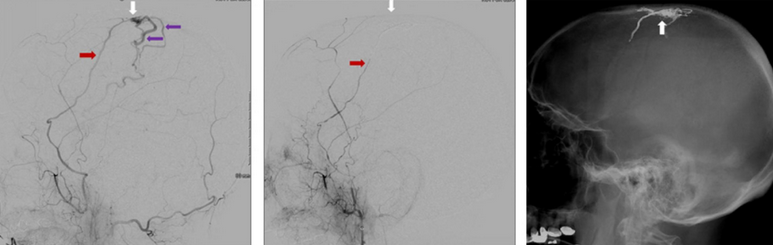

Arteriovenous fistulas are connections between two vessels that are abnormal. Dural arteriovenous fistulas, or DAVFs for short, occur when perforating veins in the dura mater of the brain’s meninges connect an artery and a vein. Arteries transport blood from the heart to the tissues, Read more…